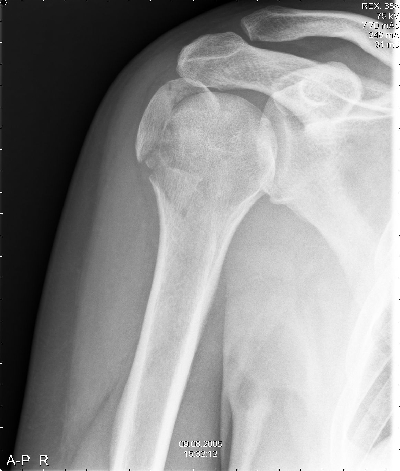

Na de ongelukige val was de arm uit de kom. |